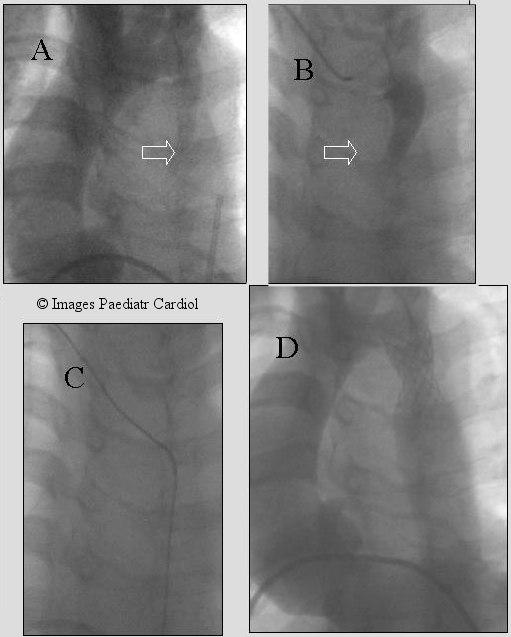

Balloon expandable stents have been used to manage coarctation of the aorta in selected patients with very encouraging results. After the successful use of the Palmaz stents in these lesions newer stents as well as modifications of the Palmaz stents have been introduced to achieve optimal results in these patients. In this review, the older as well as the newer type stents used in coarctation are discussed. Technical considerations to achieve successful stent implantation and choice is outlined.

球囊扩张式支架已被用于治疗部分主动脉缩窄患者,效果非常令人鼓舞。在成功将帕尔马兹支架用于这些病变后,已引入了更新型的支架以及帕尔马兹支架的改良型,以便在这些患者中取得最佳效果。在这篇综述中,将讨论用于主动脉缩窄的老式和新型支架。概述了实现成功支架植入的技术要点及选择。